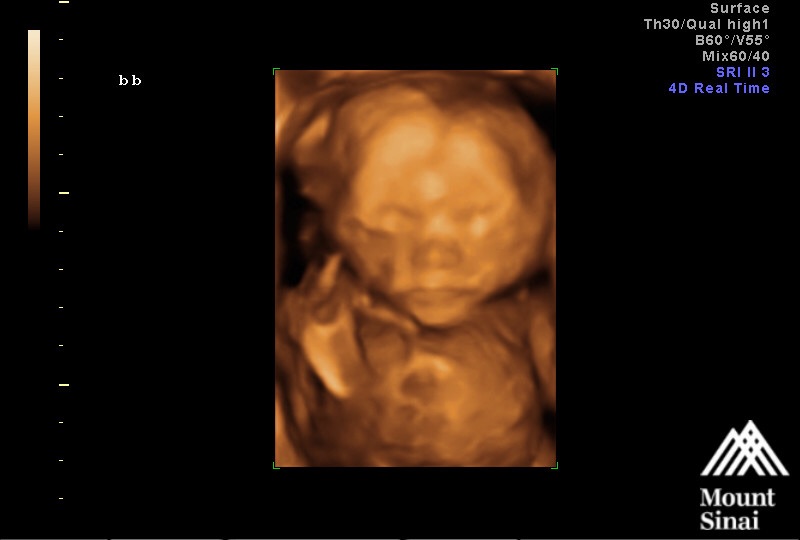

23 weeks! Please excuse my sloppiness, Im battling a nasty cold. That was the best I could do! U/S is from our Echocardiogram on Monday. Baby girl's heart looks perfect!